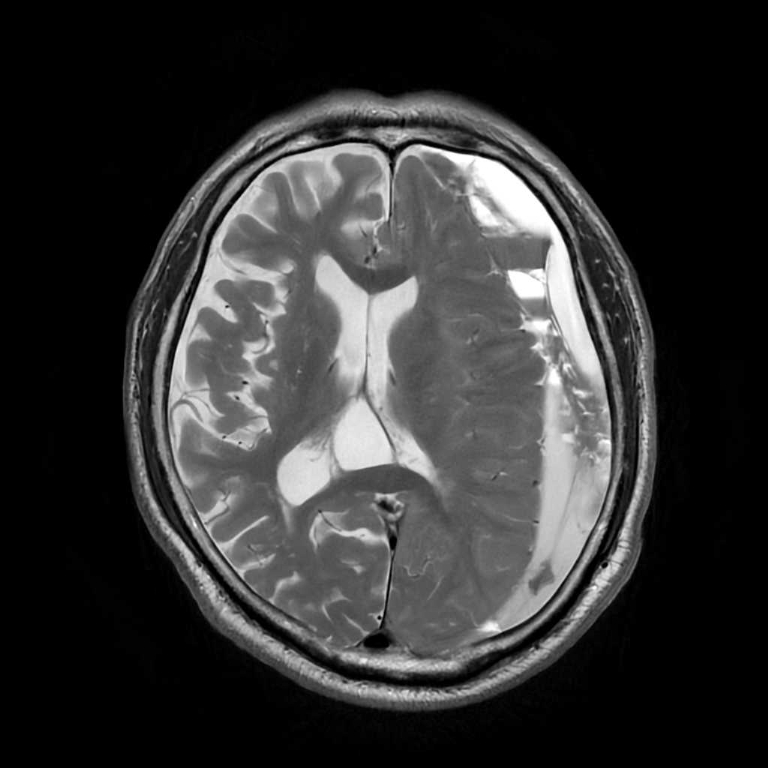

MRI検査

内科領域

頭部

脳梗塞